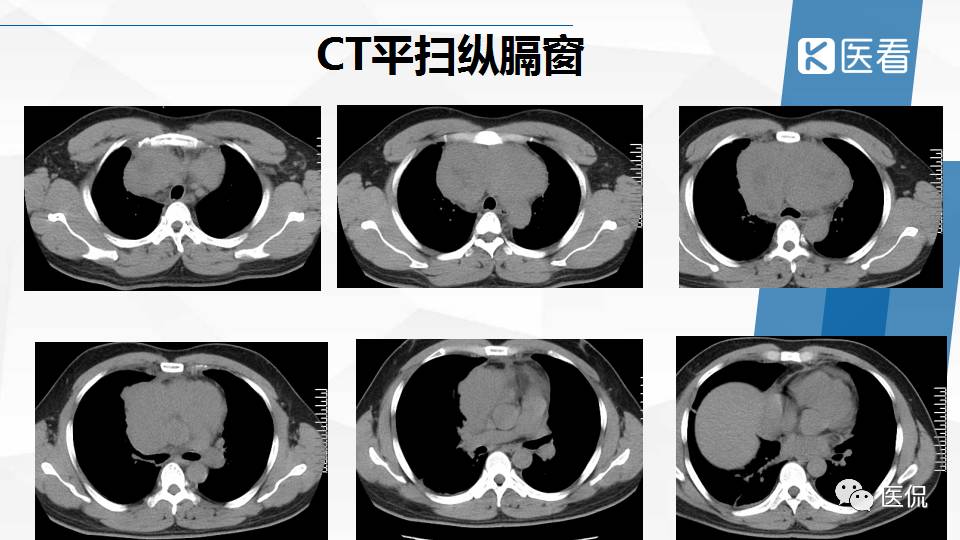

纵隔精原细胞瘤案例 (精原细胞瘤影像表现与鉴别诊断)

精原细胞瘤ct影像,精原细胞瘤影像特征